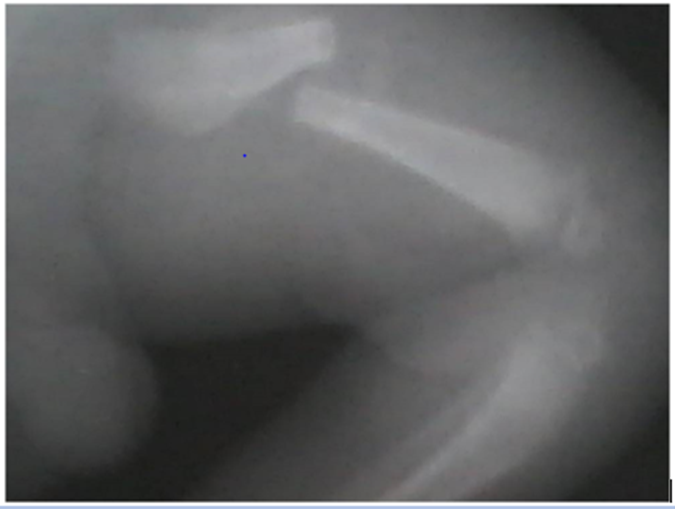

A 10 days old male neonate was brought by the parents on account of swelling of the leftt thigh and irritability which started 4 hours prior to presentation. Symptoms were noticed following circumcision done by a nurse in another hospital. Circumcision was carried out with the baby in supine position, without any form of anaesthesia. He was said to have been forcibly restrained at both thighs during the procedure by a relation. There was no history of birth trauma or deformity of the thigh from birth. On presentation, he was irritable, the right thigh was swollen with anterior angulation in the proximal part. Phallus showed a fresh circumcision wound. X-rays (Figure 1) showed a transverse, displaced fracture of the left femur, no evidence of underlying bone disease. The femoral fracture was treated with Gallow’s Traction and the circumcision wound was cleaned and dressed. He did well and was discharged after 16days.

Figure 1: showing X ray of left femoral fracture